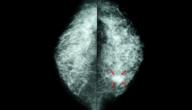

كثافة أنسجة الثدي حالة طبيعية وشائعة بين النساء يُكشَف عنها باستخدام تصوير الثدي الشعاعي أو الماموغرام، إذ تتكوّن أنسجة الثدي من غدد الحليب وقنوات الحليب والأنسجة الداعمة، وهي ذاتها نسيج الثّدي الكثيف والأنسجة الدهنية التي تُشكل الأنسجة غير الكثيفة، وتبدو نسبتها أقل من الأنسجة الدّاعمة في حال أظهر تقرير خاص يُسمى (BI-RADS) أنّ أنسجة الثّدي كثيفة بعد فحص الماموغرام أو التّصوير الشّعاعي.[١]

تُصنّف أنسجة الثدي عالية الكثافة من خلال استخدام نظام يطلق عليه اسم (BI-RADS) يساعد في تفسير نتائج التصوير الشعاعي للثدي وتشخيصها، وصُنّف نظام (BI-RADS) كثافة الثدي إلى أربع فئات:[٣]

• الفئة (A): تظهر في هذه الفئة أنسجة الثدي الدهنية بالكامل وتقريبًا يوجد عند 10% من النساء.

• الفئة (B): تظهر مناطق متناثرة من أنسجة الثدي الكثيفة والأنسجة الضامة الليفية والموجودة في 40% من النساء.

• الفئة (C): تظهر أنسجة الثدي عالية الكثافة غير متجانسة، وتوجد الأنسجة الغدية والأنسجة الضامة الليفية والموجودة في 40% من النساء.

• الفئة (D): تظهر أنسجة ثدي عالية الكثافة بشكل كبير والموجودة في 10% من النساء.

إذا كانت أنسجة الثدي عالية الكثافة؛ فهذا يعني أنّ النتائج تظهر ما بين الفئة (C) والفئة (D).

هل تؤثر أنسجة الثدي عالية الكثافة في الفحوصات؟

قد تسبب أنسجة الثدي الكثيفة صعوبة الكشف عن سرطان الثّدي خلال التصوير الإشعاعي للثدي فتظهر الأنسجة الكثيفة بيضاء، وقد تبدو في بعض الأحيان في صورة كتل أو أورام بيضاء اللون؛ مما يُصعّب التميز بينها وبين أورام سرطان الثدي، والنساء المصابات بأنسجة الثدي عالية الكثافة أكثر عرضة للإصابة بسرطان الثدي مقارنة باللواتي لديهن أنسجة ثدي منخفضة الكثافة، لكن لا يوجد في الوقت الحالي سبب ارتباط كثافة أنسجة الثدي بالإصابة بسرطان الثدي،[٤] فوفقًا للمعهد الوطني للسرطان؛ فإنّ 40-50% من النساء اللواتي يعانين من أنسجة الثدي عالية الكثافة فإنّ 20% من هذه الحالات قد تكون فيها النساء مصابات بسرطان الثدي، لكن بسبب صعوبة رؤية هذه الأنسجة بالتصوير الإشعاعي لا يحدث التشخيص، وقد وجدت الدراسات أيضًا أنّ التصوير الإشعاعي للثدي الرقمي والتصوير ثلاثي الأبعاد أفضل للكشف عن السرطان المرتبط بأنسجة الثدي عالية الكثافة؛ لأنّ الصور الرقمية أكثر وضوحًا.[٥][٦]